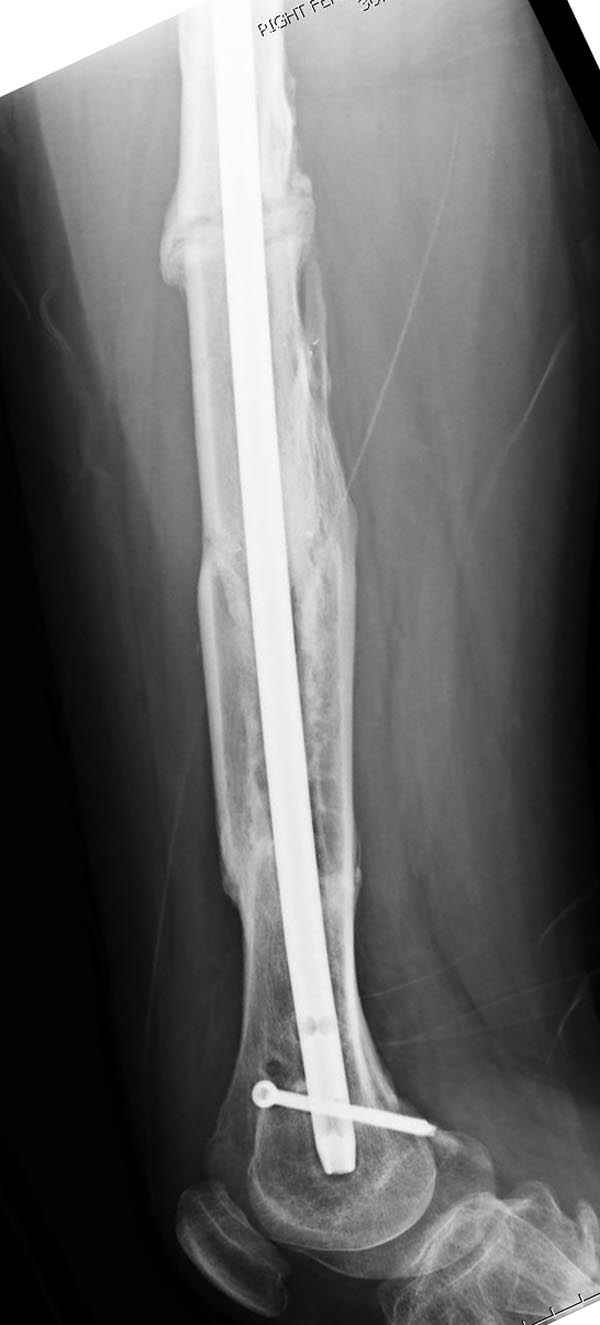

Представляю снимки больного с политравмой: леченного в другом мед.учреждении по поводу открытого перелома бедра, сперва аппаратом наружной фиксации, затем пластиной. Обратился к нам через 8 месяцев после удаления пластины с проблемой несросщего перелома бедренной кости, без клинических проявлении к инфицированию (не все снимки сохранены)

Рутинный интрамедуллярный остеосинтез с расверливанием и с фиксацией реконструктивным трокантерик штифтом (рис №1, №2),

если первые 4 месяца послеоперационного периода проходил без проблем, но на 5 месяце появились боли в дистальном отделе бедра и температура, т.е. симптомы медуллярного инфицирования (рис №3, №4).

Замена реконструктивного штифта “Custom made Nail” с антибиотиком (рис №5, №6),

после промывки канала с рассверливанием внутреннего кортекса, через 4 недели антибиотический штифт удалили, оспалителный процесс остановлен и бедро сросся.

Мы не дождались “Happy End”, у больного IQ в пределах 70%, через 6 месяцев вернулся после небольшой травмы, споткнувшись получил перелом

того же бедра (рис №7).

На следующий день произвели интрамедуллярный остеосинтез: этапы во время операции (рис №8, №9)

и последующих снимках (рис №10, 11, 12, 13) перелом сростается и передвигается с полной нагрузкой.

При обзоре причин перелома, на снимке №2 обнаружили, что один из стержней аппарата наружной фиксации проходил только через передний кортекальный слой, что создало стрессовую зону на бедре и в результате перелом из-за незначительной травмы.